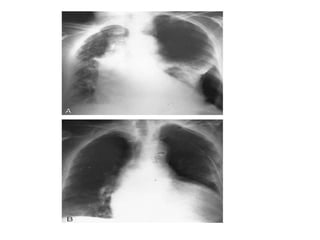

RADIOGRAPHICDIAGNOSIS

1- CXR

The standard procedure in making the diagnosis.

 It should be upright and preferably in the posteroanterior

projection. It is possible to miss a pneumothorax in a

semisupine portable anteroposterior view. If the patient

cannot be upright, a lateral decubitus view with the suspect

side positioned up may be helpful.

 A giant bulla can mimic a pneumothorax. Subtle lines demarcate

a bulla, which tends to be surrounded by thickened visceral pleura.

In addition, a pleural line can frequently be seen with lung

markings visible beyond the suspected bulla (double wall sign)

• British Thoracic Society guidelines for the

management of spontaneous pneumothorax,

recommend defining pneumothoraces as:

I. small defined as small rim of air around the

lung

II. moderate as lung collapsed halfway towards

the heart border

III. complete as airless lung, separate from the

diaphragm.

2- CT CHEST

 CT is seldom required for routine diagnosis of SP

 it can help differentiate between SP and a giant bulla.

 Controversy exists about the significance of routine chest CT to evaluate

for subpleural blebs. However identification of large or multiple subpleural

blebs on CT is an indication for early surgical intervention to prevent

recurrence.